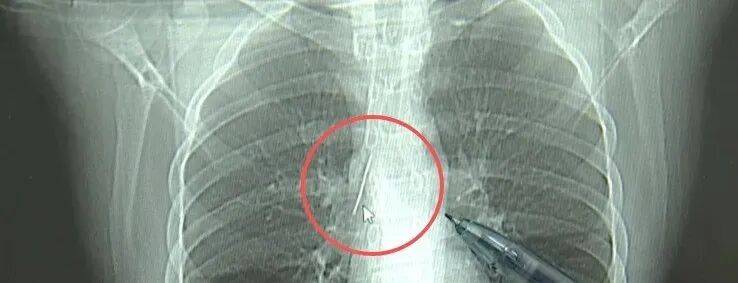

近日,安徽17岁小伙小陆参加征兵体检,胸片结果显示:胸腔内有一处金属高密度影,形态细长,像一根针上海资讯

进一步的CT检查确认,异物是一枚金属针,斜插在肺组织内,位置十分凶险上海资讯

杭州市第一人民医院心胸外科副主任冯兴说:“我们看到这个针的尖锐部,正好指向他体内的一个大血管,边上是上腔静脉和胸主动脉,因此这个针稍有不慎,就有可能造成周边血管的损伤,甚至危及生命上海资讯。”